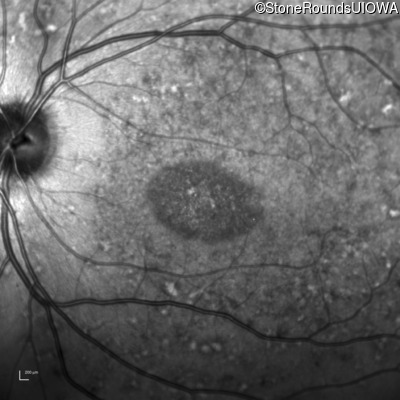

Infrared Fundus Photograph - Right - 20/125 sc

Exemplar